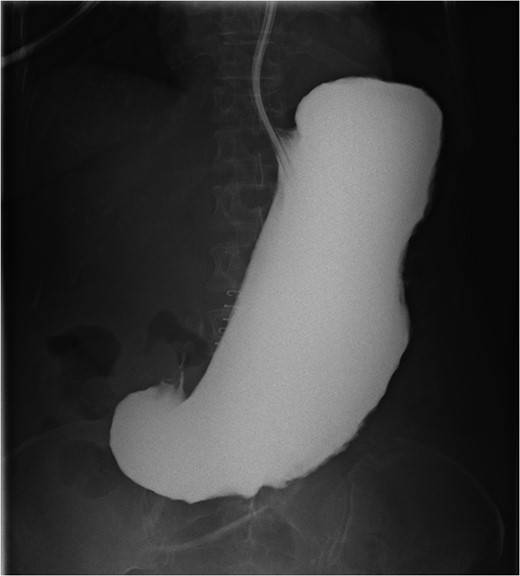

Post-operatively the patient did well without apparent complication. An upper gastrointestinal series was performed on post-operative day 5 (Fig. 2) which was negative for leak but notable for very limited transit of contrast into the duodenum 2 h after administration. Her pathology returned negative for H. Pylori, negative for malignancy, but positive for abundant amyloid deposits. Ultimately, she was discharged home to hospice care given her overall decline.

Upper gastrointestinal series 2 h after gastrograffin contrast administration down nasogastric tube demonstrates no leak and no passage of contrast from severe gastroparesis.